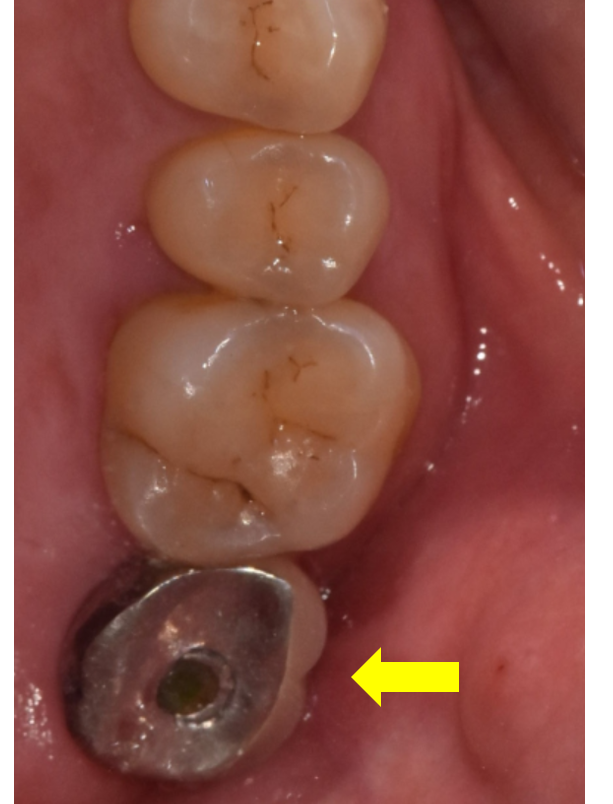

250709

임플란트 구멍이 탈락하면서

음식물이 들어가 냄새가 나서 알아차리시거나...

(구멍 근처가 까끌 거리면 바로 병원에 방문해주셔야해요!)

계속된 악취로 보철을 제거해서 청소해줄 때가 있는데요.

보통 보철물을 제거하고 나서

내부를 소독해줄 때 많이 아시게 됩니다.